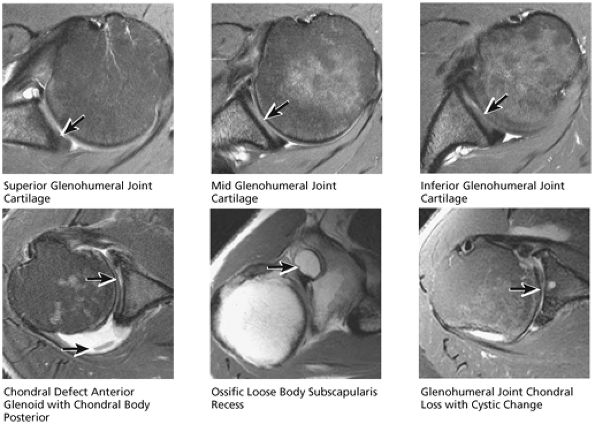

The suprascapular artery and nerve are located posterior and medial to the superior glenoid rim. The dark, low-signal-intensity labrum is located at the level of the glenohumeral articulation, inferior to the coracoid. Normally, the anterior and posterior labrum have well-defined triangular shapes. The posterior labrum may be smaller and more rounded than the anterior labrum. With internal rotation, however, the anterior labrum appears to be larger than the posterior labrum.

-

Glenohumeral articular cartilage follows the concave shape of the glenoid cavity and demonstrates intermediate signal intensity on T1-weighted images and bright signal intensity on T2*-weighted images. Articular cartilage of the glenoid margin of the anterior labrum may be mistaken for a tear. Articular cartilage of the glenohumeral joint is better evaluated on FS PD-weighted FSE sequences.